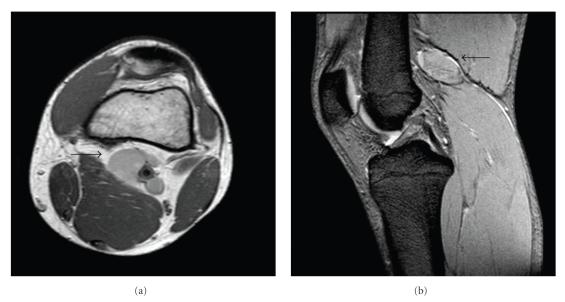

We report a case of a 21-year-old man with a popliteal venous aneurysm of the left popliteal fossa, with local symptoms and pain during palpation. Early diagnosis is fundamental in order to prevent the thromboembolic events or other major complications. Duplex scanning, Computed Tomography scanning, and Magnetic Resonance imaging are considered to be important non-invasive diagnostic methods for the diagnosis of PVA. The Angio Computed Tomography acquisition confirmed a 36 mm x 17 mm oval mass in the left popliteal fossa continuous with the popliteal veins. This lesion had presented contrast enhancement only in delayed acquisition (180 sec) and so appeared to be a true venous aneurysm and no arterial. The PVA was repaired surgically via a posterior approach to the popliteal fossa. A 4 x 2 aneurysm was identified. In the same time open tangential aneurysmectomy and lateral vein reconstruction were realised. This case is interesting because the Angio Computed Tomography study, in delayed acquisition, has allowed a correct diagnostic assessment of PVA and the surgical treatment.

我们报告一例21岁男性患者,其左腘窝患有腘静脉瘤,伴有局部症状及触诊疼痛。早期诊断对于预防血栓栓塞事件或其他严重并发症至关重要。双功扫描、计算机断层扫描和磁共振成像被认为是诊断腘静脉瘤的重要无创诊断方法。血管计算机断层扫描成像证实左腘窝有一个36毫米×17毫米的椭圆形肿块,与腘静脉相连。该病变仅在延迟采集(180秒)时出现对比增强,因此似乎是一个真正的静脉瘤而非动脉瘤。通过腘窝后方入路对腘静脉瘤进行了手术修复。发现一个4×2的动脉瘤。同时进行了开放性切线动脉瘤切除术和外侧静脉重建。该病例很有意思,因为血管计算机断层扫描研究在延迟采集时能够对腘静脉瘤进行正确的诊断评估并指导手术治疗。